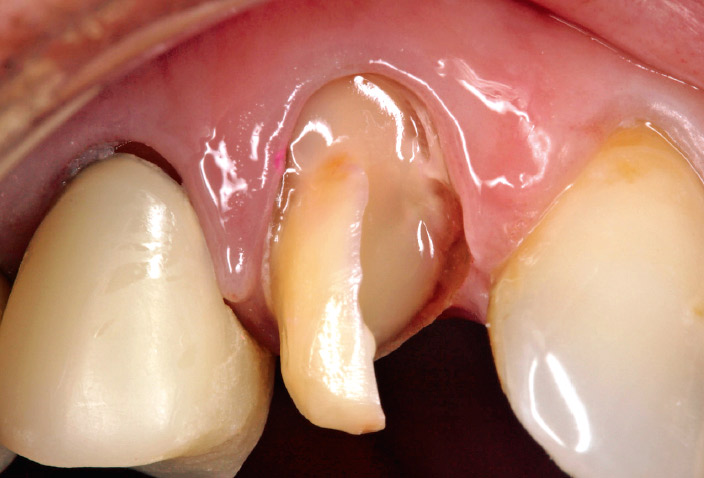

65歳、女性。根管処置歯の3 。

う蝕染色液にて脱灰象牙質を除去し、コアレジンフローによる髄腔保持型のレジン支台築造を選択した。

積層法3回でコア部の築盛を行ったが、レジンの垂れも少なく、短時間で支台築造が完了した。

図11-a 3 根管処置歯。髄腔保持型の築造窩洞形成終了。